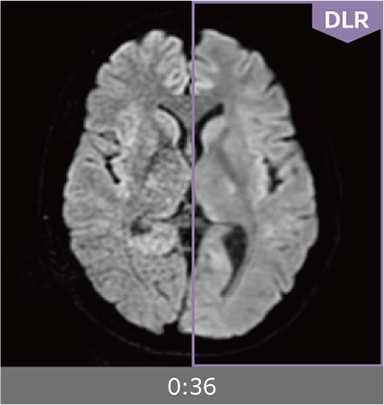

Combining high-speed imaging technology with Deep Learning reconstruction technology*3, Advanced Reconstruction with Deep Learning Synergy DLR, enables shorter exams and reduces image noise.

Images can be obtained at high speed by combining two proprietary technologies: IP-RAPID, which reduces imaging time while maintaining image quality, and Synergy DLR, which uses deep learning technology*6 to improve image quality

Under-sampling reduces imaging time, and iterative reconstruction with IP-RAPID reduces noise and artifacts.

In addition, Synergy DLR, an image reconstruction technology utilizing deep learning technology, further eliminates noise and produces images that are easier to use in making a diagnosis.